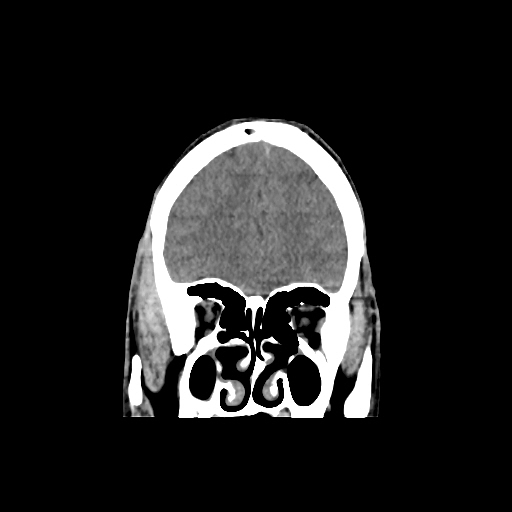

CT scan of brain images: